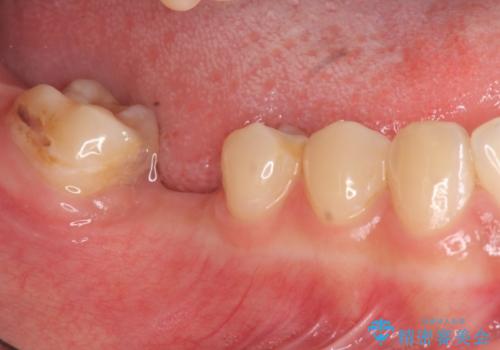

- 虫歯で歯を失い、インプラント治療を希望され来院されました。

吸収した骨を造骨にて補い、インプラントによる機能回復を計画します。